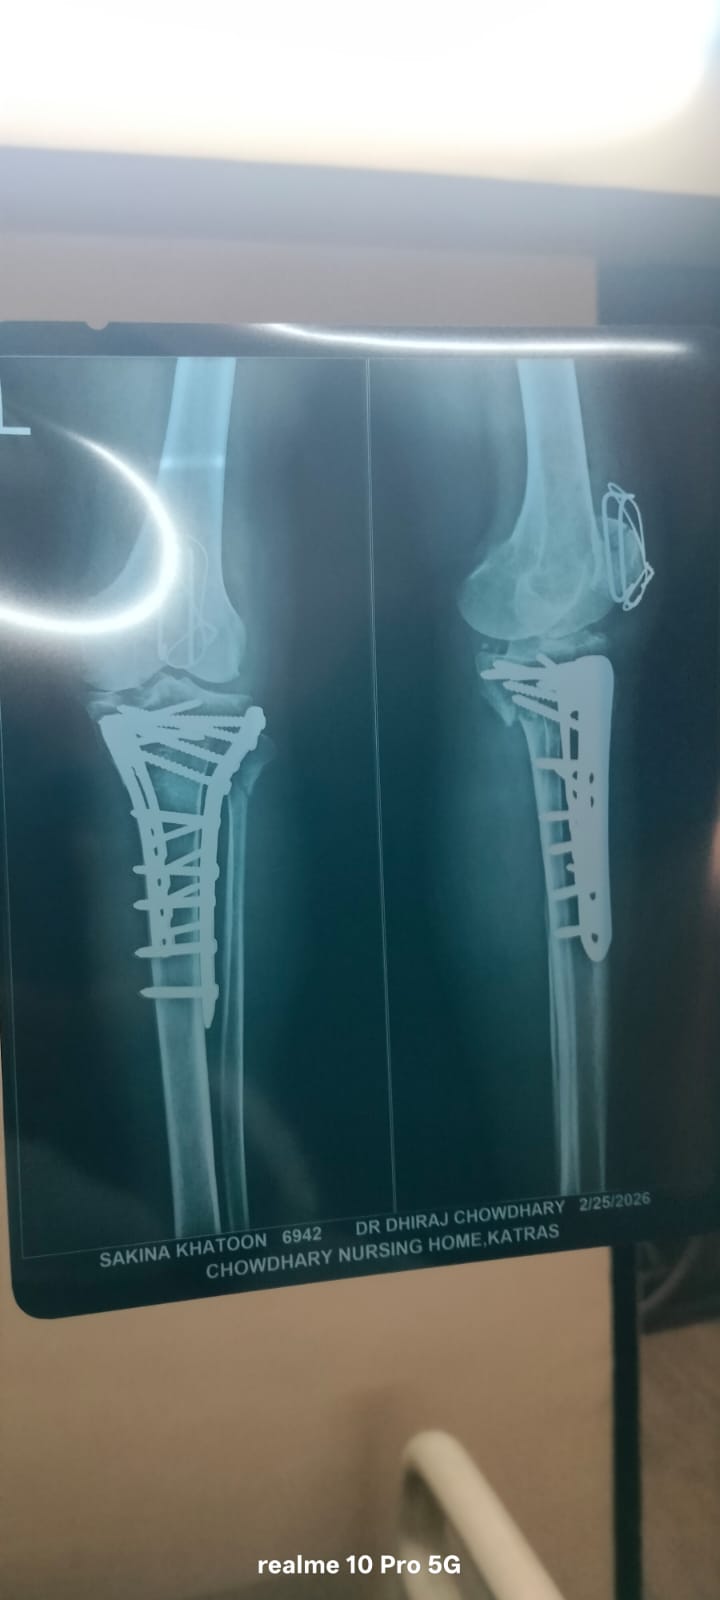

The Imam Sahab of a prominent masjid is currently going through a very difficult time. (Name withheld for obvious reasons.) His mother has suffered a serious fall from the terrace, resulting in fractures to two bones. She requires urgent surgery and medical care. We humbly request your kind support in helping to raise the necessary funds for her treatment.